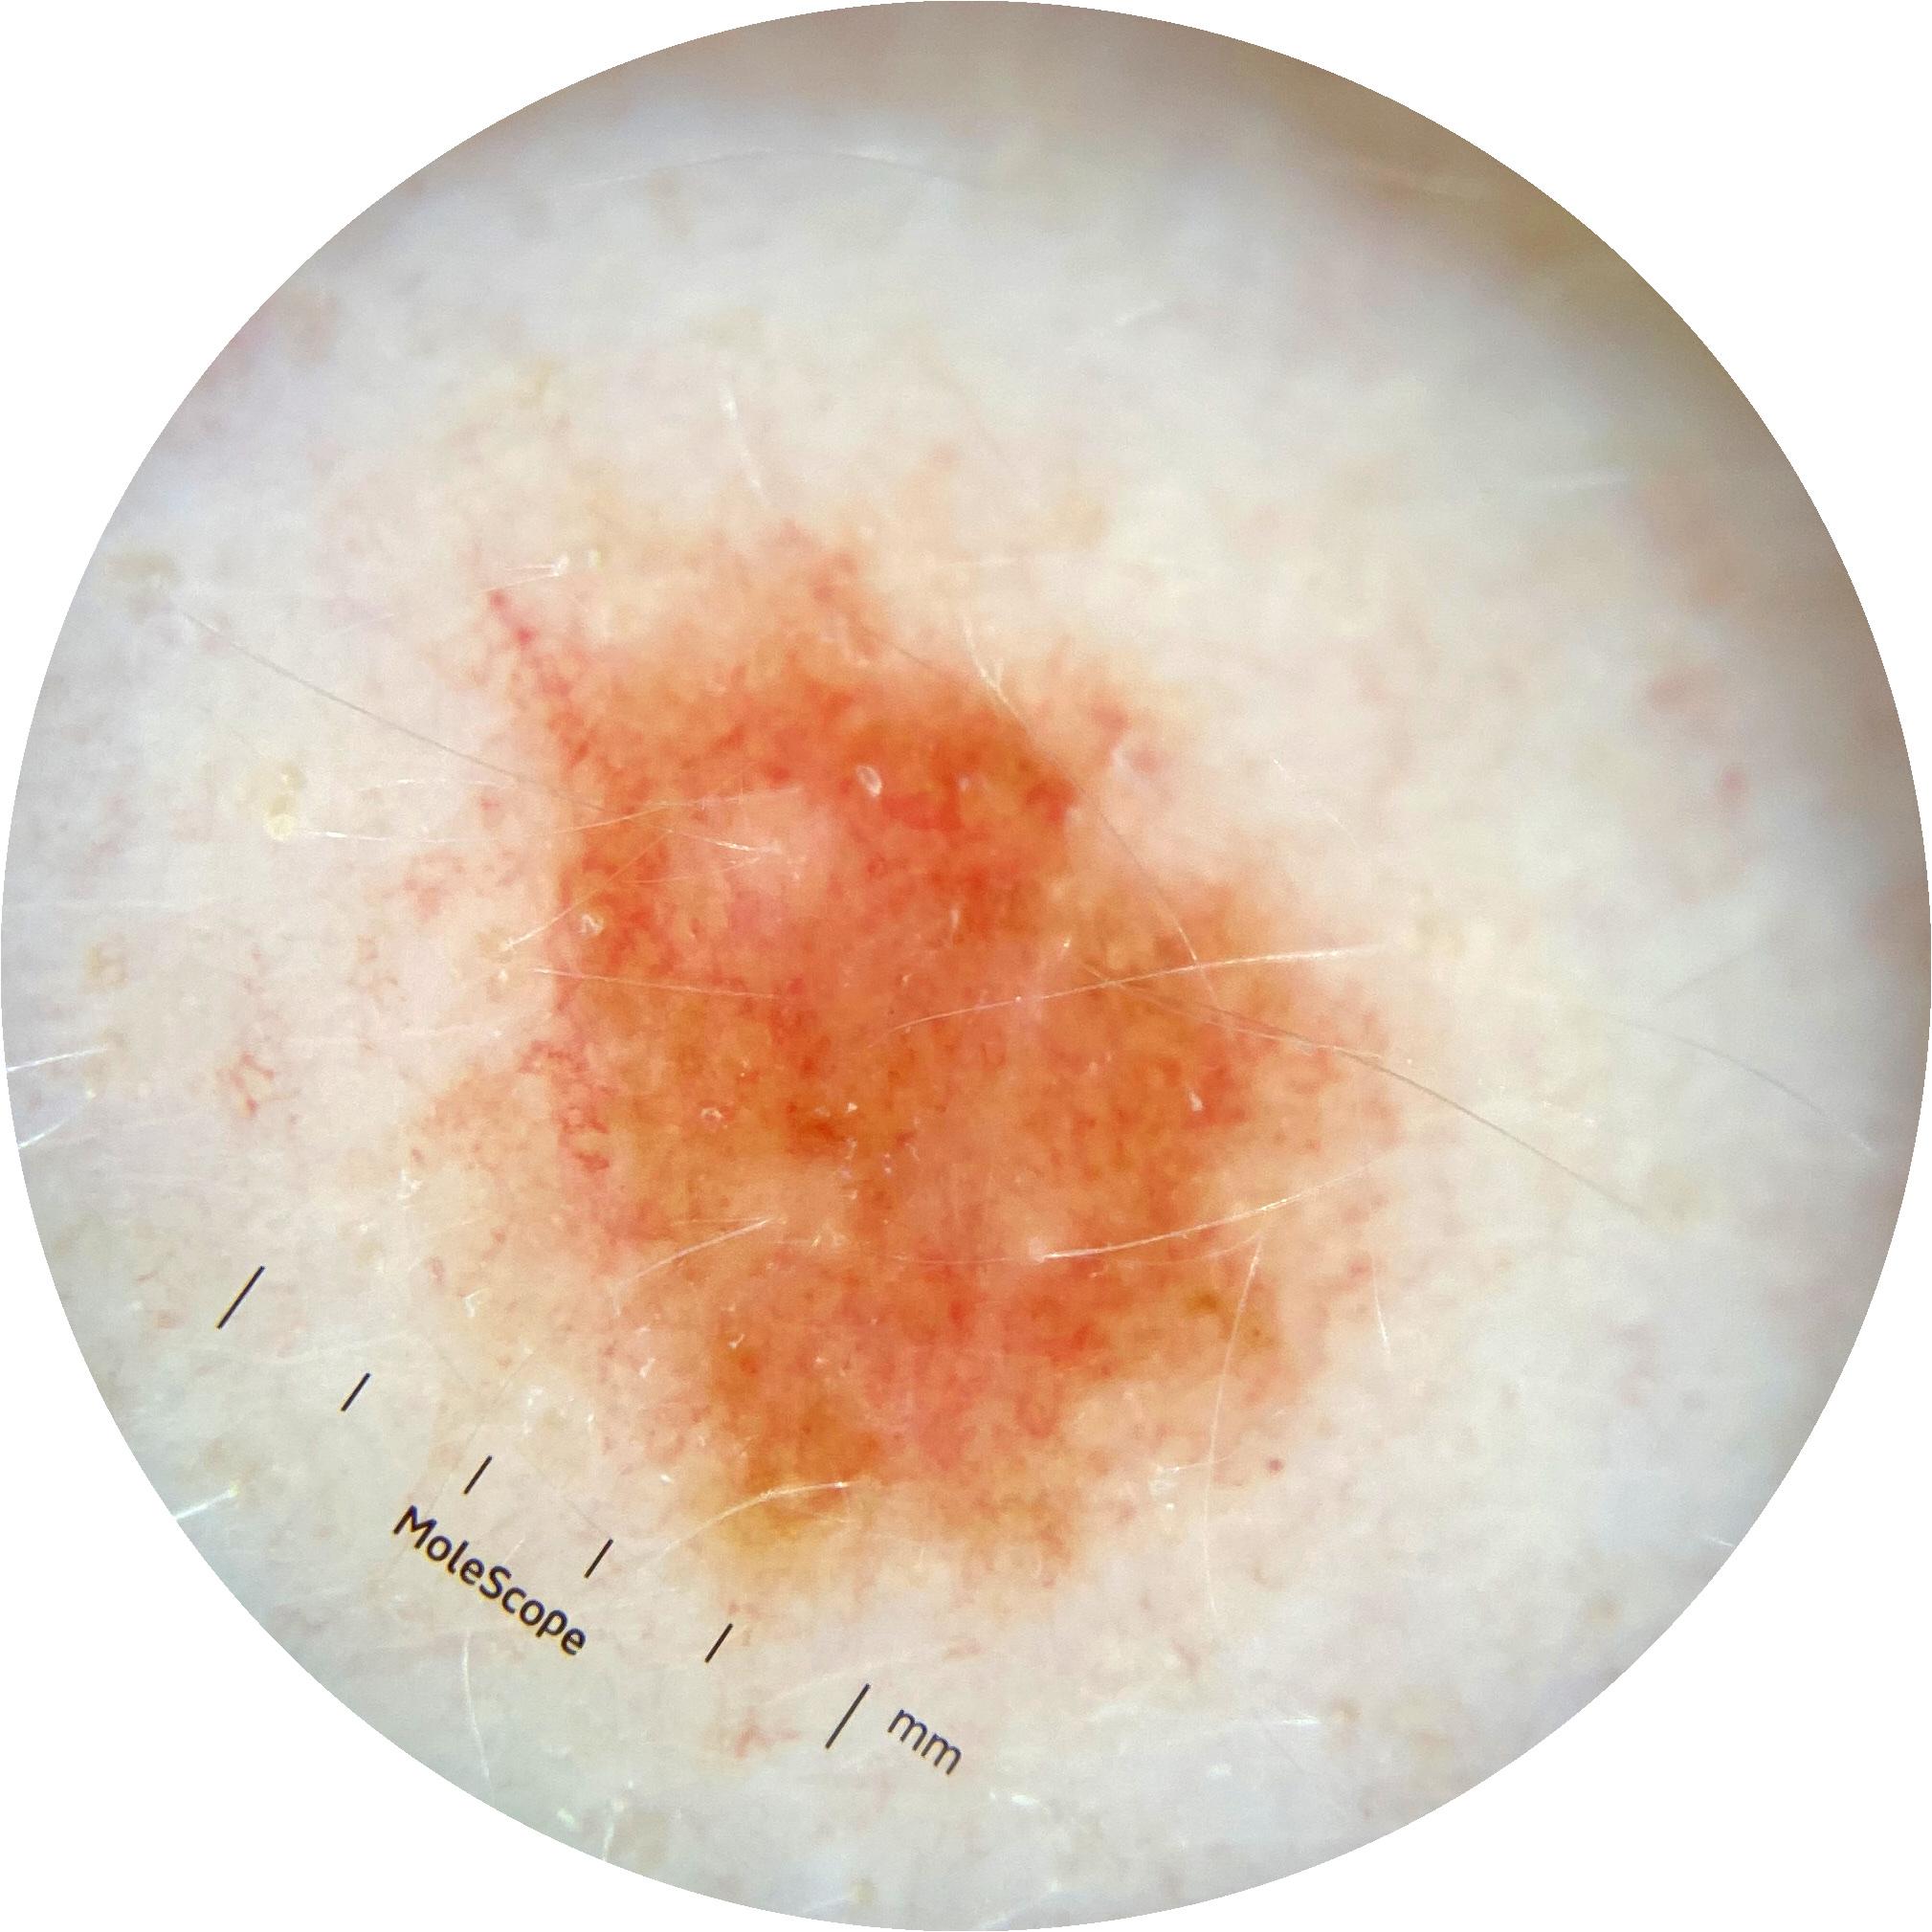

ISIC_1376863

IP_6274125

IL_8319447

Clinical

Field Value

acquisition_day 229

age_approx 40

anatom_site_general oral/genital

anatom_site_special oral or genital

concomitant_biopsy False

diagnosis_1 Benign

diagnosis_confirm_type single image expert consensus

family_hx_mm True

image_manipulation instrument only

image_type dermoscopic

lesion_id IL_8319447

patient_id IP_6274125

personal_hx_mm True

sex female